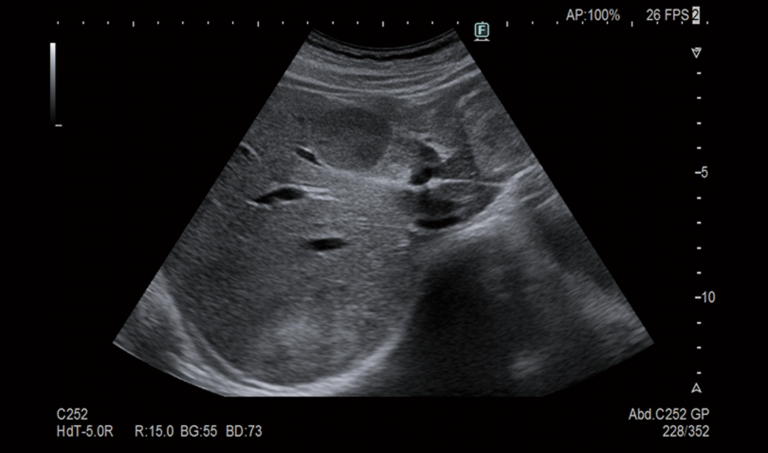

យើងខ្ញុំសូមណែនាំឧបករណ៍មួយក្នុងចំណោមឧបករណ៍ទំនើបដែលកំពុងត្រូវបានប្រើប្រាស់នៅគ្លីនិក។ គឺម៉ាស៊ីនអ៊ុលត្រាសោន FUJIFILM ARIETTA650 DeepInsight SE ។

ដូចដែលអ្នកបានដឹងហើយថា អ៊ុលត្រាសោន គឺជាវិធីសាស្ត្រដែលប្រើរលកសំឡេងដើម្បីថតរូបភាពនៅខាងក្នុងរាងកាយ។ ហើយម៉ាស៊ីនអ៊ុលត្រាសោននេះ ទោះបីជាស្ថិតនៅក្នុងម៉ាសុីនតូចក៏ដោយ ប៉ុន្តែត្រូវបានរួមបញ្ចូលជាមួយនឹងបច្ចេកវិទ្យាអ៊ុលត្រាសោនទំនើបបំផុតរបស់ជប៉ុន។

ចូរយើងទាំងអស់គ្នាក្រឡេកមកមើលរូបភាពអ៊ុលត្រាសោនខាងក្រោម៖

ទោះបីជាយើងមិនចេះមើលរូបភាពអ៊ុលត្រាសោនក៏ដោយ ក៏មិនពិបាកនឹងកត់សម្គាល់ពីគុណភាពរបស់រូបថត និងចំណុចលម្អិតផងដែរ។

ឧបករណ៍នេះអាចបង្ហាញភាពមិនប្រក្រតីយ៉ាងច្បាស់ដែលម៉ាស៊ីនចាស់មិនអាចរកឃើញ។ គុណភាពរបស់រូបភាពច្បាស់រហូតដល់ថ្នាក់ដូចជាយើងកំពុងសម្លឹងមើលរាងកាយដោយផ្ទាល់ ដោយមិនមែនតាមរយៈម៉ាស៊ីននោះទេ។

អ៊ុលត្រាសោនត្រូវបានធ្វើឡើងនៅលើផ្ទៃស្បែក មិនឈឺចាប់ មិនធ្វើឲ្យពិបាកទ្រាំ ឬសម្ពាធណាមួយលើរាងកាយឡើយ។ ទោះជាយ៉ាងណា ឧបករណ៍នេះនៅតែអាចរកឃើញកោសិកាមហារីកថ្លើម ដុំសាច់នៅក្នុងរាងកាយ គ្រួសក្នុងថង់ទឹកប្រមាត់ ដុំពក ភាពមិនប្រក្រតីនៅក្នុងក្រពះ លំពែង ស្បូន… និងការប្រែប្រួលតូចៗជាច្រើនទៀត។

ហើយសំខាន់ជាងនេះទៅទៀត នៅទីនេះ រូបភាពអ៊ុលត្រាសោនទាំងនេះត្រូវបានអាន និងវិភាគដោយអ្នកបច្ចេកទេស និងវេជ្ជបណ្ឌិតជប៉ុនដែលមានបទពិសោធន៍ ល្បីឈ្មោះ ដោយមិនមើលរំលងចំណុចលម្អិតណាមួយឡើយ។